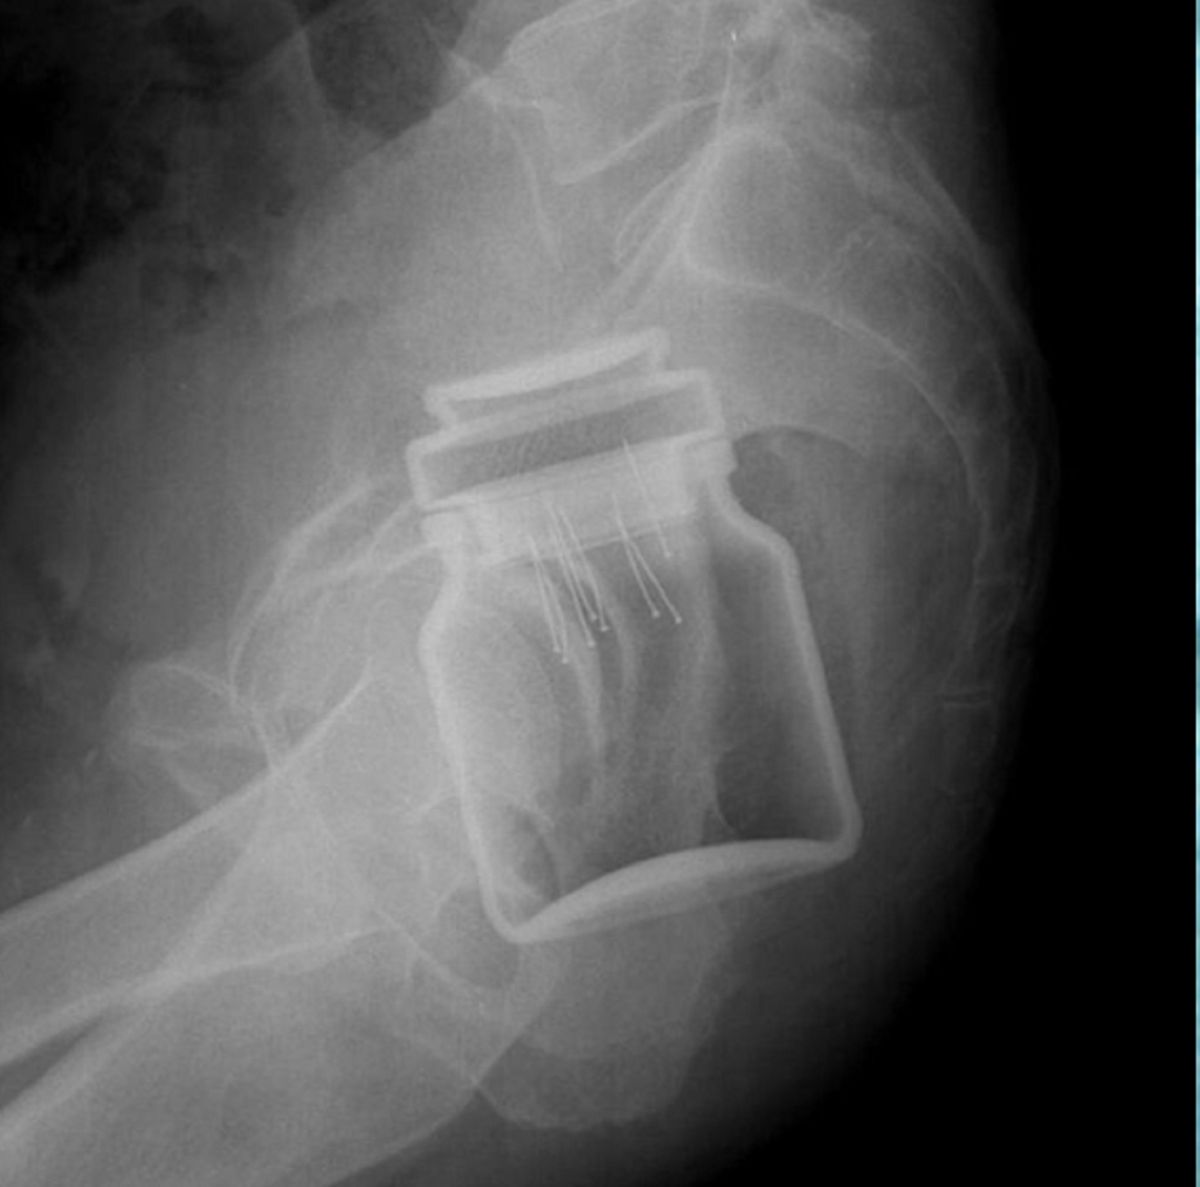

/ 8Słoik z kawą

Obraz

© imgur.com

Podobno pacjent był tak zawstydzony, że nawet nie próbował się tłumaczyć.